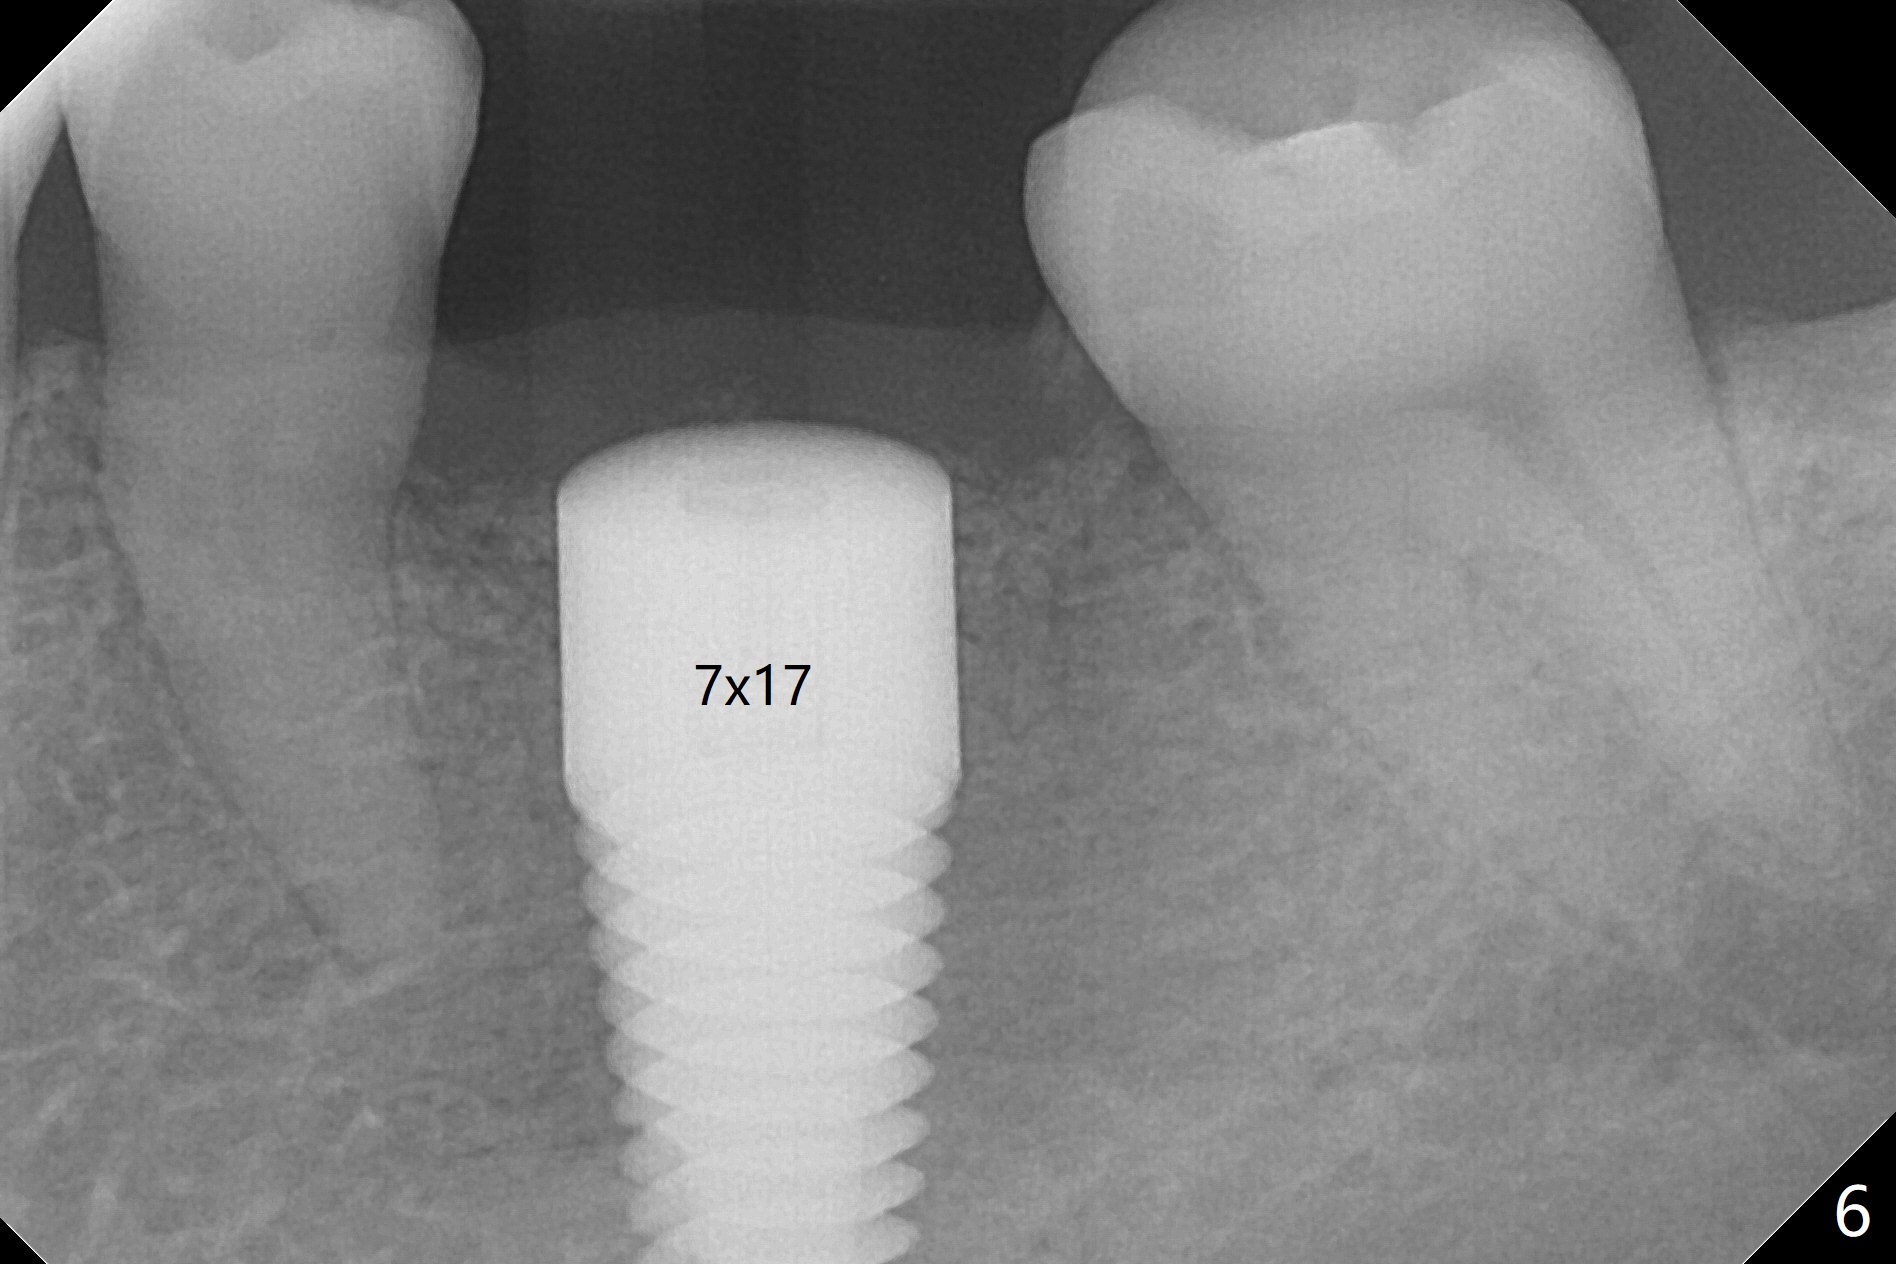

After 4.0x10 mm drill with 9 mm offset for 4.5x10 mm bone-level implant at #19, a 4.5x17 mm tissue level tap is inserted with apparently low torque (probably without reaching the depth). When a 4.5x14 mm tissue level implant is placed with high torque, a 4.5x7.3 mm drill is used for ~ 6.5 mm. The implant loses the primary stability with over-insertion (Fig.1). When an abutment is placed, the implant is critically loose. Mixture of autogenous bone, Osteogen and allograft is placed in the osteotomy. The implant regains stability with better placement level for restoration (Fig.2). In fact the bone density around the implant increases (Fig.2 *). For the first 7 days postop, the patient has to take Advil. When he returns for follow up 8 days postop (Fig.3), the pain decreases, while there is minor degree of lower lip paresthesia. Medrol Dose Pak and Tylenol III are prescribed. The implant is loose 24 days postop; after removal of the implant and apparently infected bone graft, a 7x14 mm dummy implant is inserted with <20 Ncm and 3-4 mm clearance (Fig.4). A longer dummy implant seems to improve stability (Fig.5). So does the definitive implant (Fig.6,7, 25 Ncm), but it is placed low. The gingiva looks healthy 13 days postop (2nd placement). A healing cap will be placed for restoration ~ 3 months postop. CT will be taken if the implant needs to be backed up to determine whether there is enough bone buccolingually. Due to coronavirus and prolonged placement of a healing abutment with poor oral hygiene, the buccal gingiva of the implant is erythematous 1 year postop (Fig.8 healing cap just removed) with bone loss (Fig.9,10 *). Sticky bone seems to be necessary. A 6x5 mm abutment with slots will be placed to hold periodontal dressing in place.